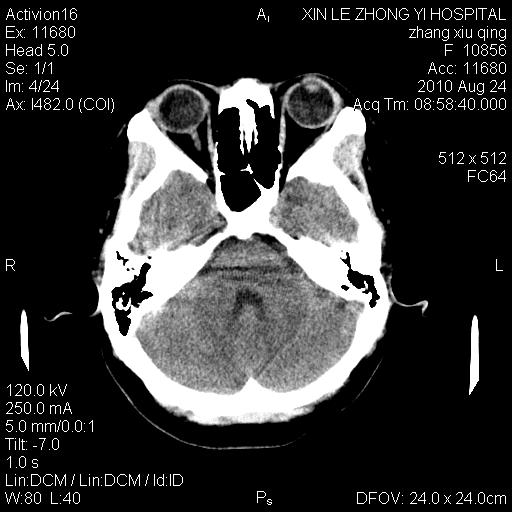

标题: CT28569:看看鞍上池正常吗 [打印本页]

标题: CT28569:看看鞍上池正常吗

女 24 偶有头晕

病史?感觉有水肿,炎症或转移

伪影多,建议行mri!

建议薄层扫描或mr

没什么!只是扫描层面与听眦线不平行